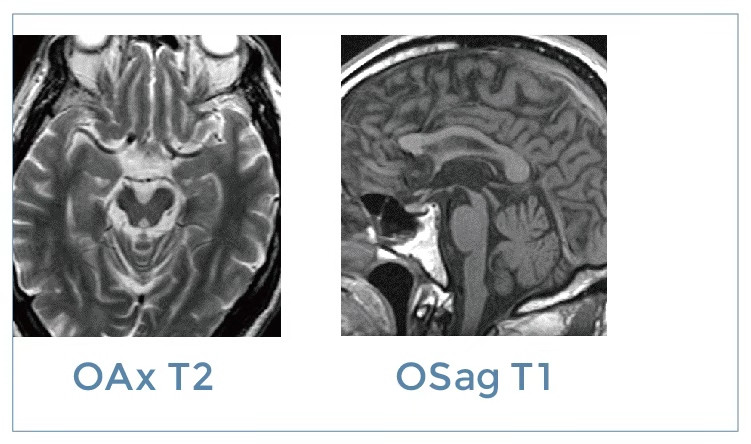

【朗润影像档案】20191115磁共振影像病例结果讨论

【朗润影像档案】磁共振影像病例分享(编号20191115)